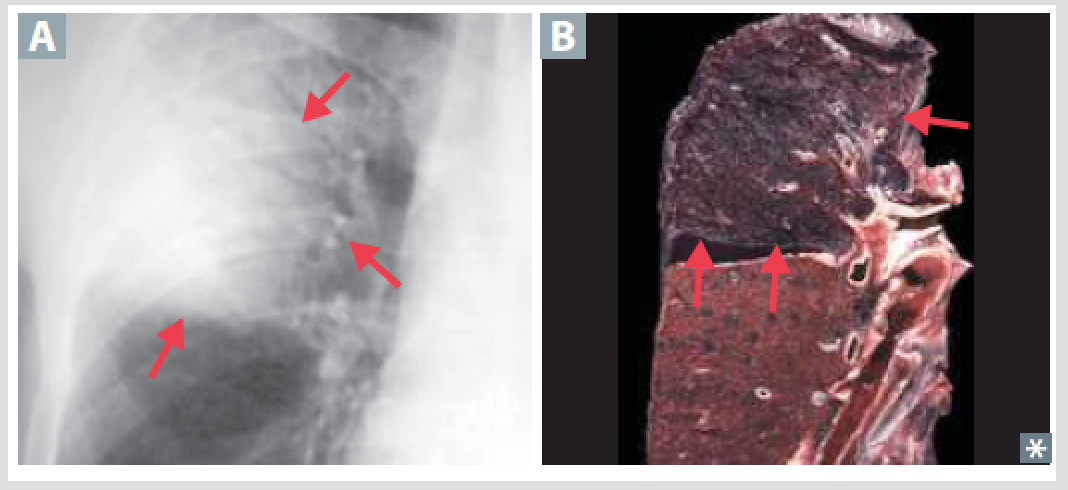

Localized collection of of PUS within parenchyma caused by aspiration of oropharengeal contents. Especially in alcoholics

Lung Abscess